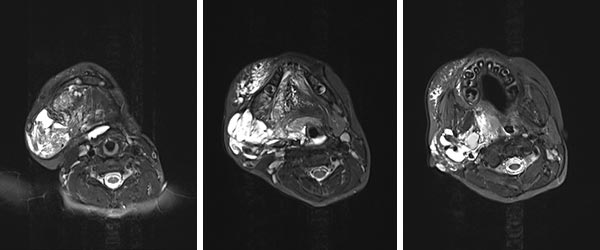

Axial T2-weighted, fat-saturated MRI at 6 years of age, after a total of 4 sclerotherapy procedures, shows a clear improvement, especially of the macrocystic parts of the lymphatic malformation. The positive effect on the upper airways, which are now no longer constricted, is also striking.